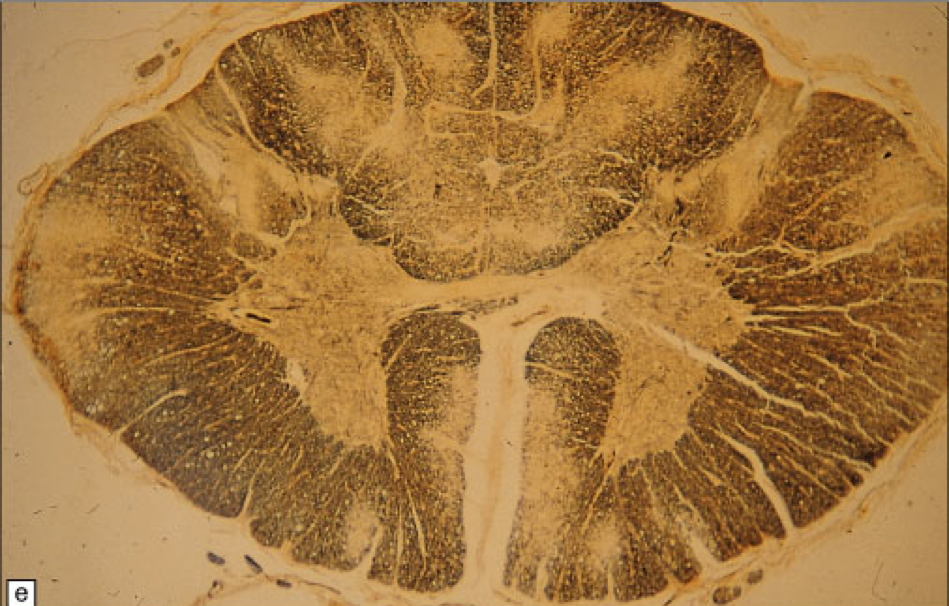

What is this?

Tabes Dorsalis

Tabes dorsalis, also known as syphilitic myelopathy, is a slow degeneration (specifically, demyelination) of the neural tracts primarily in the dorsal columns (posterior columns) of the spinal cord (the portion closest to the back of the body) & dorsal roots.